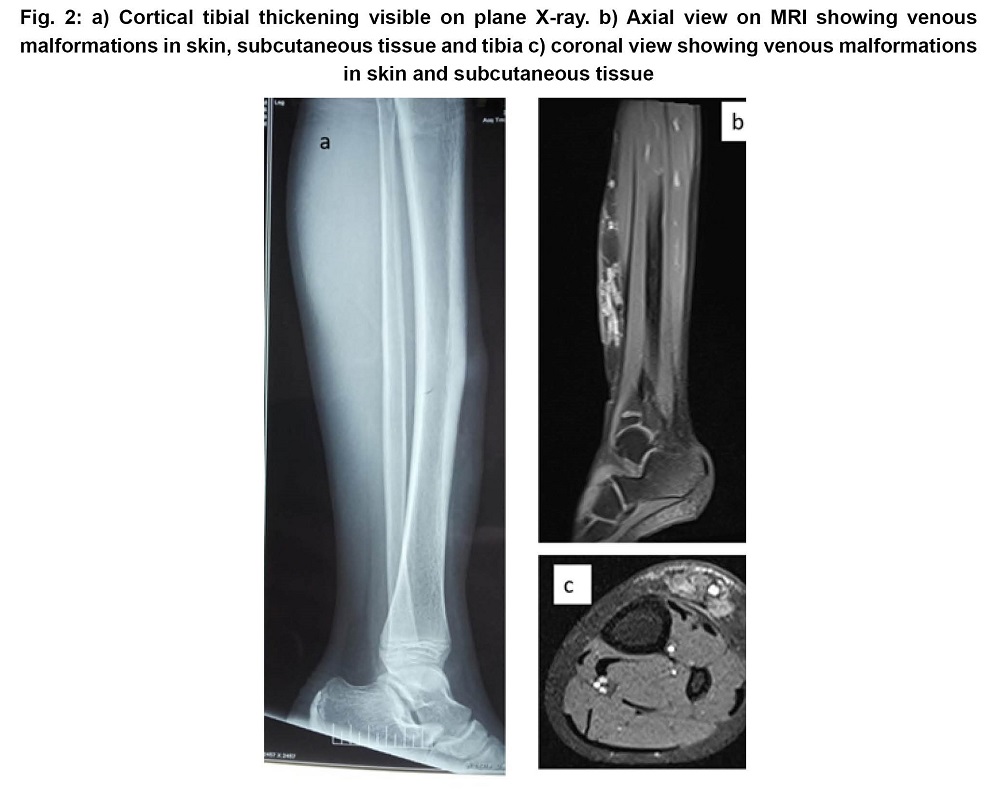

Vascular anomalies are the commonest developmental disorders. Venous malformations (VM) result due to dysmorphogenesis in the development of veins. Most commonly these disorders are localized to skin and subcutaneous tissue. Deeper venous malformation may affect the underlying muscle, bone and joints. Early terminalization of hair and increased sweating in VM plaque has been rarely reported. The present study deals with the case of a 15-year-old boy who had VM involving skin, subcutaneous tissue and bones with terminal hair and increased sweating over the plaque. Radiological examination showed bone hypertrophy with slow flow channels and phleboliths due to superficial and deep VM. He was treated with ethanol sclerotherapy.